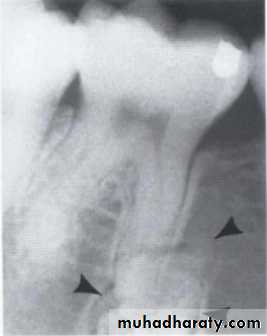

• 2.Position in the jaws:

• - Epicenter coronal to tooth- odontogenic epithelium.

• - Epicenter of the lesion is above the mandibular canal-odontogenic in origin .

• - Epicenter -below lDC- non odontogenic

principles of radiographic interpretation

Cystic ameloblastoma displaced IDC (odontogenic origin)

Epicenter coronal to tooth

(odontogenic epithelium )